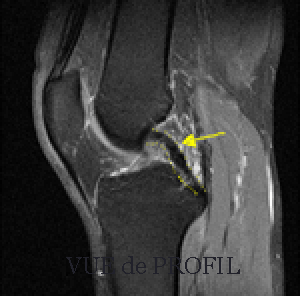

Le ligament croisé postérieur (flèche jaune sur l'irm) fait partie du pivot central du genou avec le croisé antérieur. Il stabilise le tibia sous le fémur, en empêchant le tibia de partir vers l'arrière.

Il est confirmé par l'IRM

L'IRM confirme le diagnostic, et surtout recherche les lésions associées +++, mais ne donne pas d'élément sur l'importance de la laxité.

IRM d'une fracture non déplacée de l'épine tibiale postérieure : la chirurgie n'est pas nécessaire.